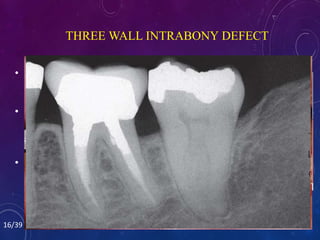

• Three-wall defects are amenable to pocket

successful in filling three-wall defects.

THREE WALL INTRABONY DEFECT

• Three-wall defectsare amenable to pocket reduction with regenerative periodontal therapy. • Bone grafts using either autogenous bone or allografts along with the use of resorbable membranes have been successful in filling three-wall defects. • If the result of periodontal therapy is stable 3 to 6 months after periodontal surgery , orthodontic treatment may be initiated. THREE WALL INTRABONY DEFECT 16/39

• #18 This patient had a significant periodontal pocket distal to the mandibular right first molar. Periapical radiograph confirmed the osseous defect. A flap was elevated revealing a deep, three-wall osseous defect. Freeze-dried bone was placed in the defect. Six months after the bone graft, orthodontic treatment was initiated. The final periapical radiograph shows that the preorthodontic bone graft helped regenerate bone and eliminate the defect distal to the molar